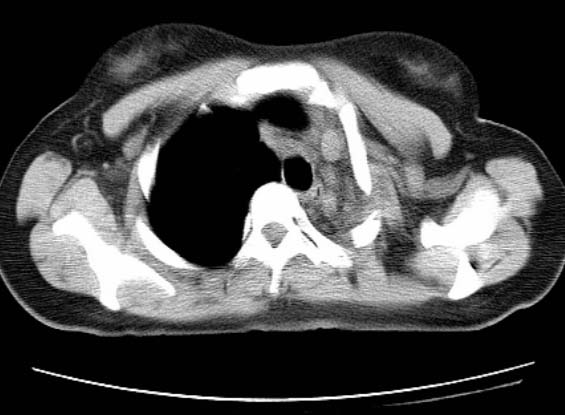

标题: CT25648:求教:是肺发育不全还是结核?

女  20岁。一月前咳血,诊“肺结核”抗痨治疗一月后,咳血停止,现复查。病人精神好。前后ct片对比未见明显变化。既往体检“正常”

1)考虑左肺结核并肺不张、支气管扩张。2)纵隔疝。

考虑左肺结核,左肺毁损,纵膈左偏,既往体检正常不可靠,tb一个月也不会这个样子的,有钙化,应该病程较长,冰冻三尺非一日之寒!

左肺发育不全。